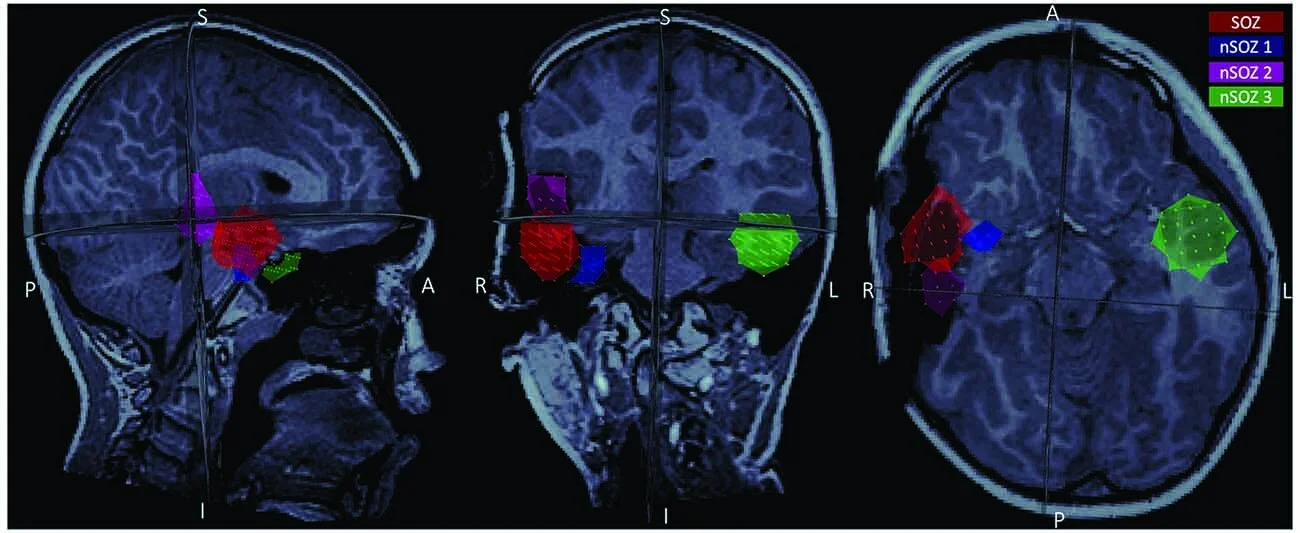

We performed a rare, 4h overnight MEG recording in an 8-yo w/ drug-resistant focal epilepsy & captured one ~45-s seizure. The patient underwent a selective right anterior temporal resection and remains seizure-free 21 months postoperatively.

The histopathological assessment confirmed frank focal cortical dysplasia (FCD) type IIa in the MEG-defined seizure onset zone (SOZ), which was based on source imaging of averaged ictal spikes at seizure onset.

Our data show that the SOZ was associated with a higher aperiodic offset & exponent during the seizure compared to control regions. Both parameters increased in all regions from 2 min before the seizure onwards.

Regions anatomically closer to the SOZ also expressed higher values compared to contralateral regions, potentially indicating ictal spread. We also show that narrow-band power changes were caused by these fluctuations in the aperiodic component of ongoing brain activity.

Our results indicate that the broadband aperiodic component of ongoing brain activity cannot be reduced to background noise of no physiological interest, and rather may be indicative of the neuropathophysiology of the SOZ.